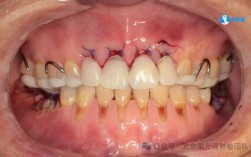

牙齿移动过程中,若施力过大、移动速度过快,或患者口腔卫生维护不当,易引发牙周组织损伤,表现为牙龈萎缩(牙根暴露,牙齿敏感)、牙槽骨吸收(X光片可见牙槽骨高度降低)、牙周袋形成(牙龈与牙齿间缝隙加深,易藏食物残渣),严重时,牙齿因失去骨支持而松动,甚至脱落,正畸装置(如托槽、弓丝)若长期刺激牙龈,可能导致牙龈增生或炎症,进一步破坏牙周健康。

正畸失败最直接的后果是牙齿排列异常未纠正或出现新的问题,常见表现包括:牙齿反弹移位(如原本内收的门牙再次外凸、牙缝重新出现)、咬合干扰(后牙咬合时某颗牙齿过早接触,导致咀嚼受力不均)、深覆颌或深覆盖复发(上下牙垂直或水平覆盖关系未稳定)、开颌(上下牙无法正常咬合,出现缝隙)等,此类问题多因矫正方案中未充分考虑牙齿稳定性(如未解决骨性问题、支抗设计不足)、保持器佩戴时间不够或终身维护中断,导致牙齿在肌肉力量或咬合压力下逐渐移回原位。

正畸移动牙齿过程中,牙根尖端可能出现吸收(牙根长度变短),严重时牙根呈“钝圆形”,影响牙齿稳定性,牙根吸收多与施力过大、移动速度过快、个体易感性(如部分患者牙根天生较细)有关,若矫正装置安装不当(如托槽粘贴位置错误),可能磨损牙釉质,甚至导致牙齿折裂。